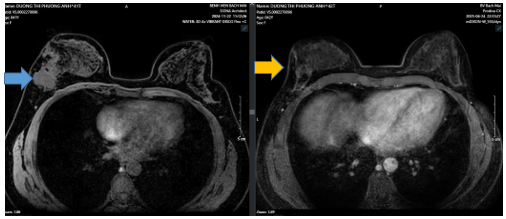

- MRI vú trước điều trị:

Hình 1:

Vú phải vị trí 1/4 dưới ngoài, cách núm vú 15mm có khối ~ 70x59x37mm, tổn thương xâm lấn da (đường kính 34mm. Nằm sát khối lớn, vị trí trung tâm ngoài, cách núm vú 13mm có nốt 7x10mm, ngấm thuốc mạnh ở pha sớm. Hố nách bên phải có vài hạch thuộc chặng 1 ~9x14mm, còn rốn hạch, hạch thuộc chặng 2 ~5mm, ngấm thuốc mạnh sau tiêm.

Hình 3:

Trước điều trị khối u vú phải ~70x59x37mm (mũi tên xanh), xâm lấn da ~34mm. Hạch thuộc chặng 1lớn nhất ~9x14mm, hạch chặng 2 ~5mm. Sau điều trị u vú phải ~16x23x36mm (sau điều trị mũi tên vàng), tổn thương xâm lấn da ~ 25mmHố nách bên phải chặng I có vài hach, còn rốn hạch vỏ hạch dày, lớn nhất ~ 4x6mm.